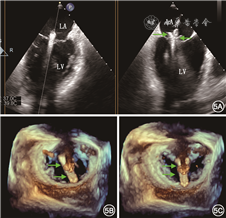

通常TTE检查即可对MR病因、Carpentier分型、反流程度以及左心室大小和功能等进行初步评估,对拟行经导管治疗的重度MR患者,术前推荐行TEE检查对二尖瓣结构进行更为精细的评估。3D TEE可同时观察到二尖瓣叶的所有区域,有助于病变区域的准确定位,有研究表明,在病变定位的精确性方面3D TEE优于TTE和2D TEE[22](图3)。此外,3D TEE血流图像能较准确地显示MR反流束的位置、宽度以及数目,有助于预测二尖瓣钳夹所需夹合器个数[23]。

LA为左心房,LV为左心室,LAA为左心耳,AO为主动脉,C1为前联合交界区,C2为后联合交界区,A2指二尖瓣前瓣A2区,P2指二尖瓣后瓣P2区